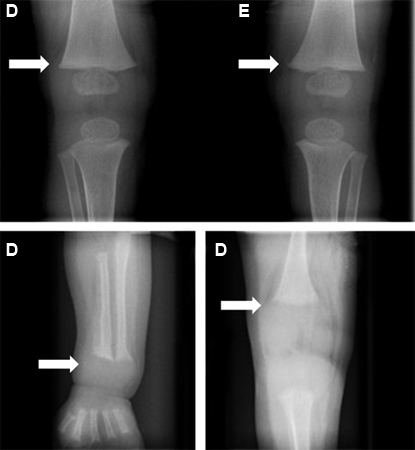

O raquitismo é caracterizado pelo crescimento tardio, dor e deformidade ósseas. O tipo de deformidade depende da situação biomecânica dos membros no momento em que a fraqueza estrutural se desenvolve. Deformidades ósseas dos antebraços e arqueamento posterior da tíbia distal podem ocorrer em lactentes, enquanto um arqueamento fisiológico exagerado das pernas (geno varo) é um achado em bebês que começaram a andar. Crianças mais velhas podem apresentar deformidades das pernas com geno valgo ou do tipo "varrido pelo vento" (deformidade em valgo de uma perna e em varo da outra).[4][5][24] O aumento metafisário pode ser observado adjacente às articulações maiores, bem como ao longo das articulações costocondrais criando o "rosário raquítico".

Sinais e sintomas de hipocalcemia, como cãibras musculares, fraqueza muscular, dormência, parestesias, espasmo carpopedal, tetania e convulsões podem estar presentes no raquitismo hipocalcêmico.[4][Figure caption and citation for the preceding image starts]: Desnutrição manifestada como raquitismo. Observe as pernas arqueadas e o punho direito aumentadoCDC [Citation ends].

[Figure caption and citation for the preceding image starts]: Desnutrição manifestada como raquitismo. Observe as pernas e os joelhos arqueadosCDC [Citation ends].

Uma radiografia de um osso longo revelando escavação, afunilamento e desgaste da metáfise é necessária para o diagnóstico. O alargamento da placa epifisária e a perda de definição da zona de calcificação provisória na interface epífise/metáfise são os primeiros sinais de raquitismo.

[Figure caption and citation for the preceding image starts]: Alterações ósseas (setas) antes (figuras inferiores) e depois (figura superior) do tratamento de raquitismoBangalore H, Bisht S, Inusa B. Rickets and tracheobronchomalacia. BMJ Case Reports 2009; doi:10.1136/bcr.01.2009.1422 [Citation ends].